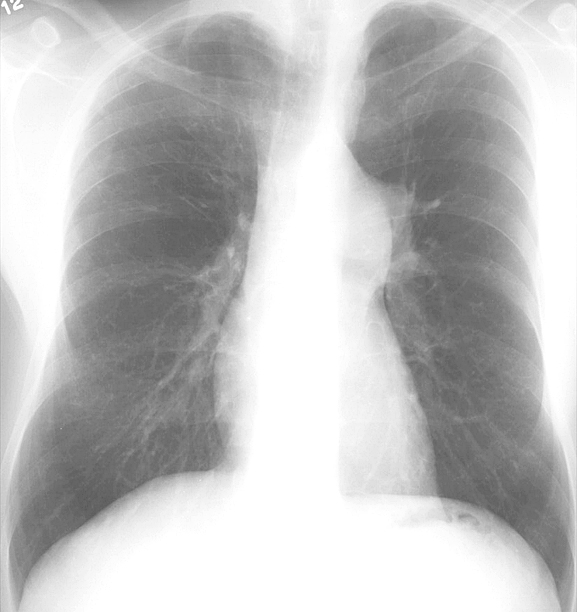

Pulm Stenosis PA